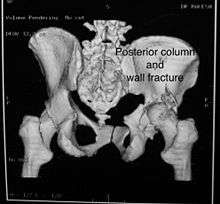

Posterior column with posterior wall / Transverse with posterior wall Fractures

These fractures are extension of elementary fractures. With involvement of posterior wall, the difficulty in treatment increases. These fractures are rarely amenable to non-surgical treatment. Due to posterior wall fracture, the hip is usually dislocated posteriorly, requiring immediate reduction of dislocation and surgical reconstruction after few days.

Cause: Posterior column with posterior wall fracture occurs due to dash board injury, while transverse fracture with posterior wall fracture occurs due to combined dash board injury and direct injury to the hip from the side.

Associated injury: to the sciatic nerve may occur

How to diagnose: Antero posterior view may give clue to these injuries, Judet views and CT scan help in knowing the extent of injury